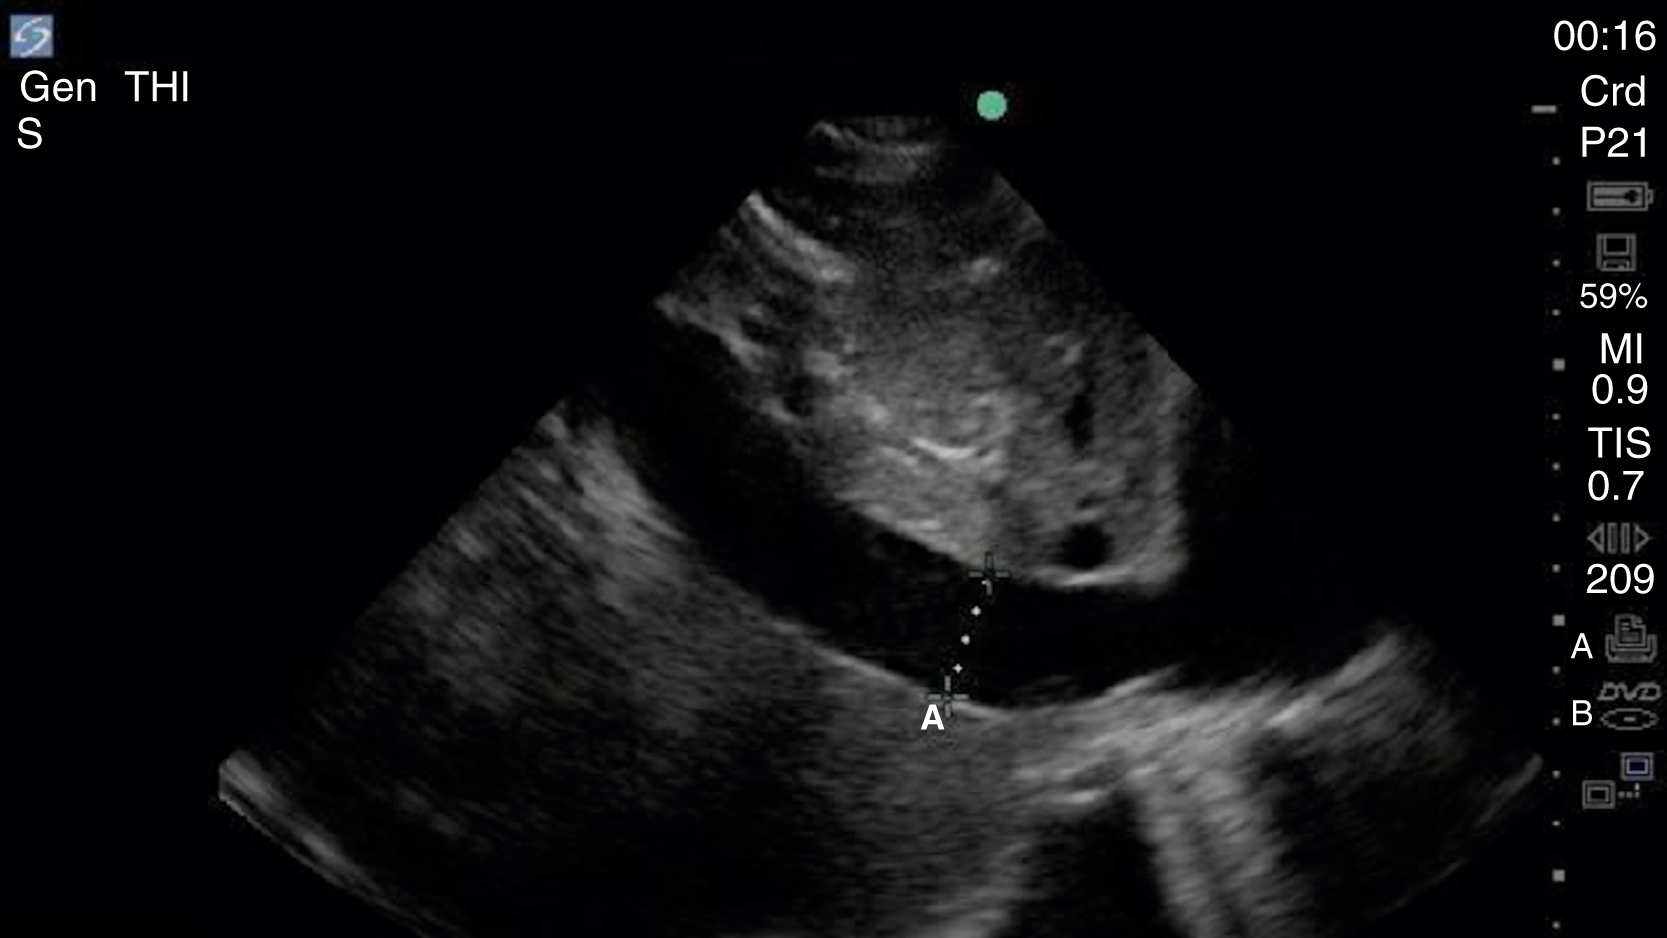

Image Acquisition

Cardiac US is performed through the transthoracic and transabdominal windows with the use of small curvilinear or phased array transducers. Typical views include the subcostal four-chamber view (subxiphoid), parasternal long-axis view ( Fig. e3.10 ; see Video e3.4 ), parasternal short-axis view, and apical four-chamber view. The subcostal four-chamber view, as in the FAST, is ideal for assessment of pericardial effusion and useful during cardiac arrest because it does not interfere with chest compressions. The long-axis subcostal view highlights the inferior vena cava (IVC) and can indicate volume status. The parasternal views are excellent windows for LV assessment. The apical four-chamber view is ideal for comparison of RV and LV sizes and function. Several US protocols have been developed to evaluate undifferentiated hypotension and can be used to narrow the differential diagnosis.

Normal parasternal long-axis view of the heart.